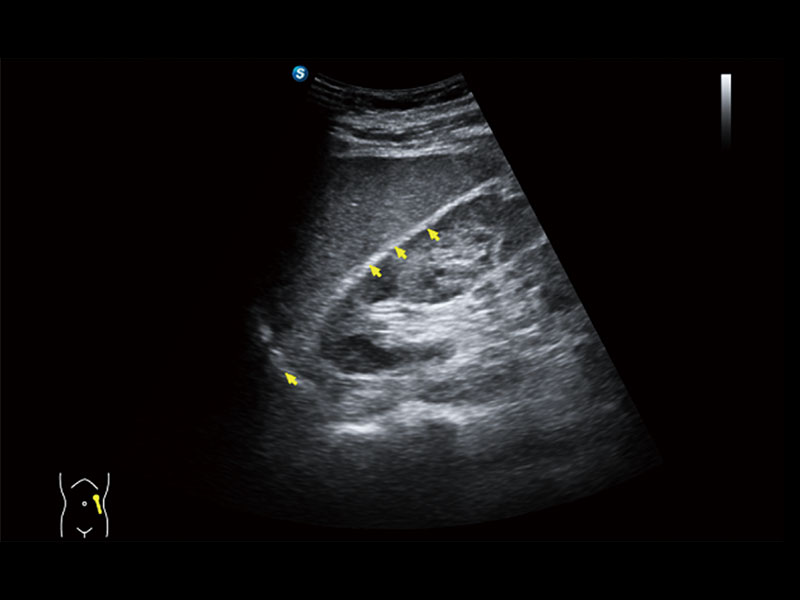

作为开立医疗全新打造的高端床旁笔记本超声,E11不仅具备卓越的图像质量,同时搭载全面高效的自动测量工具,助力医生实现更快速、更精准的床旁诊断。

E11搭载了丰富的自动化测量工具,以及专为POC科室定制的高级功能;同时配备了为急诊医师量身打造的 SonoFast急重症超声流程,以帮助临床医生最大限度的提升工作效率